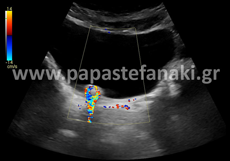

Triplex αγγείων

Για τα Triplex

• Καρωτίδων και σπονδυλικών αρτηριών

• Αρτηριών άνω και κάτω άκρων

• Φλεβών άνω και κάτω άκρων

• Οσχέου

Δεν απαιτείται προετοιμασία.

Ενώ για τα Triplex

• Νεφρικών αρτηριών

• Πυλαίας φλέβας (σπληνοπυλαίου άξονα)

• Κοιλιακής αορτής

• Λαγονίων αρτηριών

• Έλεγχος και παρακολούθηση θεραπευτικών επεμβάσεων (παρακαμπτήρια μοσχεύματα, stent) διαφόρων αγγείων στην κοιλιά

Η προετοιμασία του ασθενούς είναι απαραίτητη.

Πρέπει να είστε νηστικός-ή τουλάχιστον έξι ώρες πριν την εξέταση.

Είναι καλό από την προηγουμένη μέρα να αποφύγετε τροφές με κυτταρίνη, όπως χόρτα, όσπρια, λαχανικά και φρούτα, καθώς και γαλακτοκομικά (γάλα, γιαούρτι).

Ελεύθερα κρέας, ψάρι, κοτόπουλο, ζυμαρικά.

Δεν πρέπει να έχει προηγηθεί την ίδια ημέρα γαστροσκόπηση, ορθοσκόπηση, εξέταση στομάχου ή εντέρου.